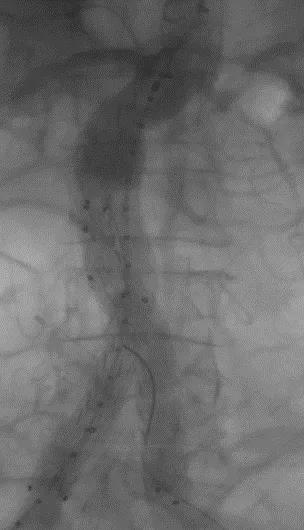

手术顺利,无内漏,持续时间1小时10分钟。术后CTA检查,支架形态良好,无内漏。详见下图:

术中影像